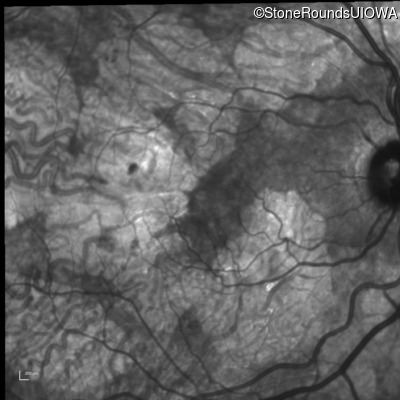

Age at visit: 51 years

OD OS

This 51 year old woman first experienced some abnormality in her distance vision when she was 27 years old. She feels that her vision has been stable since that time.